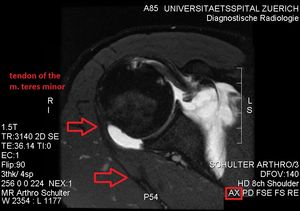

초음파검사는 작은원근의 지방 퇴행성 위축을 탐지하는 데 사용되며, 손상된 근육에서 에코 발생이 증가하고 근육 부피가 약간 감소하는 것을 볼 수 있다. 자기 공명 영상(MRI)는 신경성 근위축 진단에 유용하다. 외상 후 세포외수종은 신경 손상을 일으키며, MRI T2 강조 영상에서 신호 강도가 증가하고 T1 강조 영상에서는 정상 신호 강도를 보인다. 후방상완골선회동맥 압축과 스트레스를 유발하는 팔의 위치나 조작으로 인한 혈류 감소는 도플러 초음파 검사로 진단할 수 있다. 혈관 옆 신경이 탐지된다. 팔을 들어올린 자세에서는 액와신경혈관다발이 삼각근을 관통하기 직전 후방 겨드랑 주름에서 보이지만, 팔을 내린 자세에서는 후방 코스가 잘 보인다. 동맥의 자세한 진단을 위해서는 MR 혈관 조영술이 필요하다. 초음파 검사는 무게를 갖는 공간을 탐지한다. 근전도 검사는 신경 전도 속도 감소와 관련 근육의 신경 제거 상태를 밝혀내는 데 유용하다.[4][5]

소원근 위축은 회전근개 파열의 결과로 발생하지만, 단독적인 소원근 위축도 발견된다. 사변공증후군(quadrangular space syndrome)은 해부학적 터널을 지나는 구조물에 과도하거나 만성적인 압박을 유발한다. 액와신경과 후상완골 회선 동맥이 사변공을 통과한다. 처음엔 어깨 통증과 팔 아래 저림(paresthesia)을 느끼고, 팔을 벌리거나(abduction), 펴거나(extension), 바깥쪽으로 돌리거나(external rotation), 머리 위로 들어올리는 동작에서 느낀다. 소원근 선택적 위축이 보이면 해당 액와신경 분지나 후방상완골선회동맥의 압축과 함께 견인된다. 섬유대(fibrous band), 관절순(glenoid labrum)의 낭종(cyst), 지방종(lipoma)이나 정맥 팽창(dilated vein)은 사변공을 병리학적으로 점령하여 병을 일으킬 수 있다. 전방어깨탈구(anterior shoulder dislocation), 상완골 경부 골절, 완신경총(brachial plexus) 부상, 흉곽출입구증후군(thoracic outlet and inlet syndrome)에서도 비슷한 증상이 흔하게 나타나므로, 가능한 한 완전한 감별 진단을 위해 이러한 병리를 포함하는 것이 중요하다.초음파검사(ultrasonography)는 소원근의 지방 퇴행성 위축을 탐지하는 도구이며, 다친 근육의 에코 발생(echogenicity)가 늘어나고 근육 부피의 약간의 감소가 보이기도 한다. 자기 공명 영상(MRI)는 신경성 근위축(neurogenic muscle atrophy) 진단에 유용하다. 외상 후 세포외수종(extracellular edema)은 신경 손상을 일으키며, MRI T2 강조 영상(T2-weighted MRI) 결과에서의 신호 강도(signal intensity) 증가와 T1 강조 영상 결과물에서의 신호 강도 정상을 보인다. 후방상완골선회동맥 압축과 스트레스를 유발하는 팔 위치나 조작으로 인한 혈류 감소는 도플러 초음파 검사(Doppler ultrasonography)로 진단할 수 있다. 혈관 옆 신경이 탐지된다. 팔을 들어올린 자세에서는, 액와신경혈관다발(axillary neurovascular bundle)이 삼각근을 관통하기 바로 직전에 후방 겨드랑 주름(posterior axillary fold)에서 보일 수 있지만, 팔을 내린 자세에서는 후방 코스(posterior course)가 잘 보인다. 동맥의 자세한 진단을 위하여, MR 혈관 조영술(MR angiography)이 필요하다. 초음파 검사는 무게를 갖는 공간을 탐지하는 것이다. 추가적인 근전도 검사(electromyography)는 신경 전도(nerve conduction) 속도 감소와 관련 근육의 신경 제거(denervation) 상태를 밝혀내는 데 유용하다.[12][6]